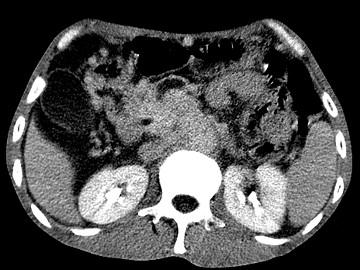

问题 女,50岁,中上腹疼痛,消瘦乏力,影像检查如下图,最佳的诊断是 ( )

选项 A、胰岛素瘤 B、腹膜后淋巴瘤 C、急性胰腺炎 D、胰腺癌并腹膜后淋巴结转移 E、慢性胰腺炎

答案 D